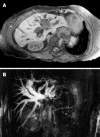

Improvements in imaging technology allow exploitation of the dual blood supply of the liver to aid in the identification and characterisation of both malignant and benign liver lesions. Imaging techniques available include contrast enhanced ultrasound, computed tomography and magnetic resonance imaging. This review discusses the application of several imaging techniques in the diagnosis and staging of both hepatocellular carcinoma and cholangiocarcinoma and outlines certain characteristics of benign liver lesions. The advantages of each imaging technique are highlighted, while underscoring the potential pitfalls and limitations of each imaging modality.